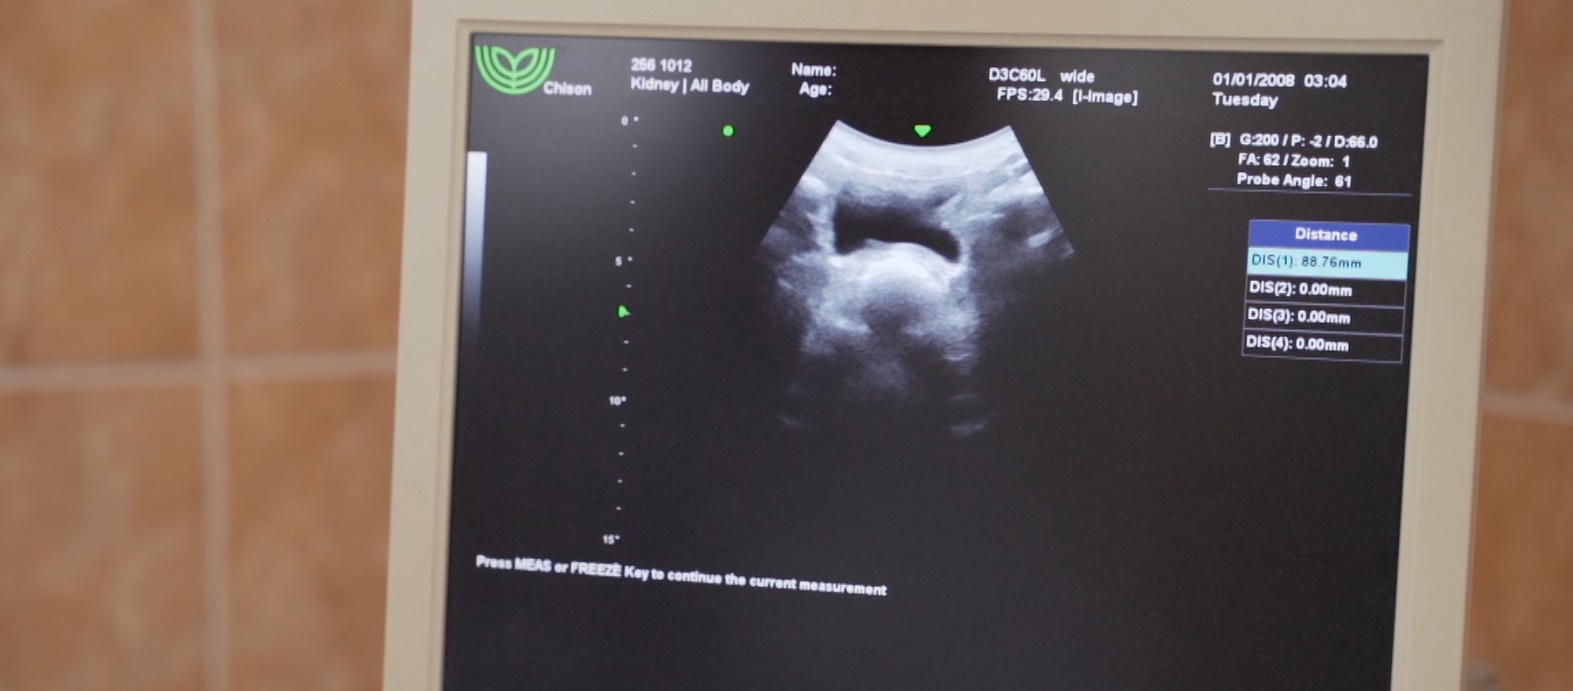

A vesebetegségek gyakran alattomosan, kifejezett tünetek nélkül jelentkeznek, sokszor csak véletlenül kerülnek felfedezésre az elvégzett labor- és ultrahang vizsgálatok során.